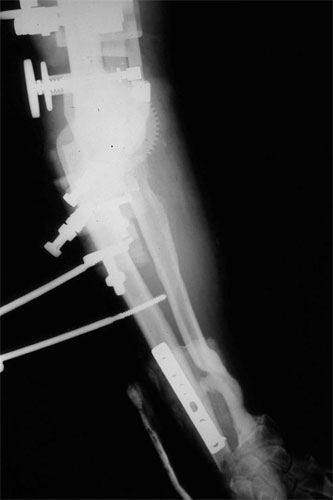

The pictures depict the application of the dynamic external fixator, which stabilized and provided early motion to the rigid elbow after aggressive release of the capsule and bone excision.

E.R. is a 26 year old male lifeguard who had a severe, unfortunate accident the first time he ever mounted a motorcycle. He was in a coma for many months with head trauma and had fractured his right elbow and forearm at the time of injury. He developed a condition called Heterotopic Ossification which meant that multiple joints “froze-up” due to deposits of calcium in the joint capsules. He was not able to walk until both hips were operated on by an internationally known hip surgeon who then referred him to Dr. Badia to address the stiff Right elbow and deformed forearm. In fact, at the initial visit, the patient stated that he had not moved the right elbow AT ALL for nearly 4 years and was unable to feed or groom himself with that hand. After a series of 3 operations to reconstruct both the elbow and forearm, this young man has gone back to swimming, work and a normal lifestyle.